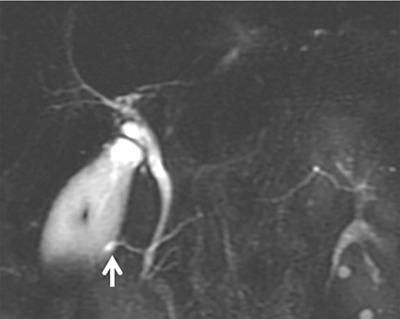

Observations: MRCP image showing the dominant dorsal duct of Santorini (arrows) draining separately into the minor papilla. The common bile duct (CBD) is joining the smaller ventral pancreatic duct through the major papilla.

Principal diagnosis: Pancreas divisum.

Image

2D MRCP image showing the pancreas is being drained by the dominant dorsal duct, which is crossing the CBD and draining at the minor duodenal papilla. In addition, there is focal dilatation (arrow) of the dorsal duct near the papilla consistent with Santorinicele.